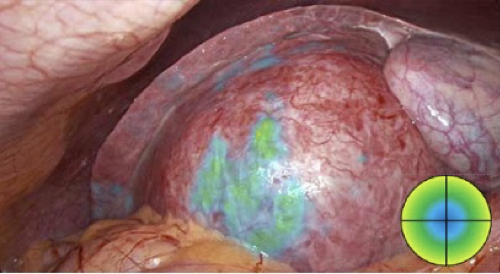

Die chirurgische ICG/NIR-Fluoreszenzbildgebung ist eine der wertvollsten Technologien bei minimalinvasiven Eingriffen, insbesondere bei der intraoperativen Visualisierung der viszeralen Perfusion, Gallenstrukturen oder der Lymphknotenkartierung.

VEQTRON™ Das Imaging System bietet vier verschiedene Anzeigemodi.